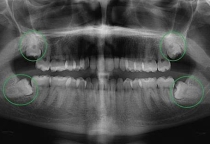

🦷 Dấu hiệu bạn cần cạo vôi răng ngay

Bạn nên kiểm tra sớm nếu có các biểu hiện:

- Răng vàng ở chân răng

- Hôi miệng kéo dài

- Chảy máu khi đánh răng

- Nướu sưng đỏ

👉 Đây là dấu hiệu viêm nướu giai đoạn đầu, cần xử lý sớm để tránh biến chứng.